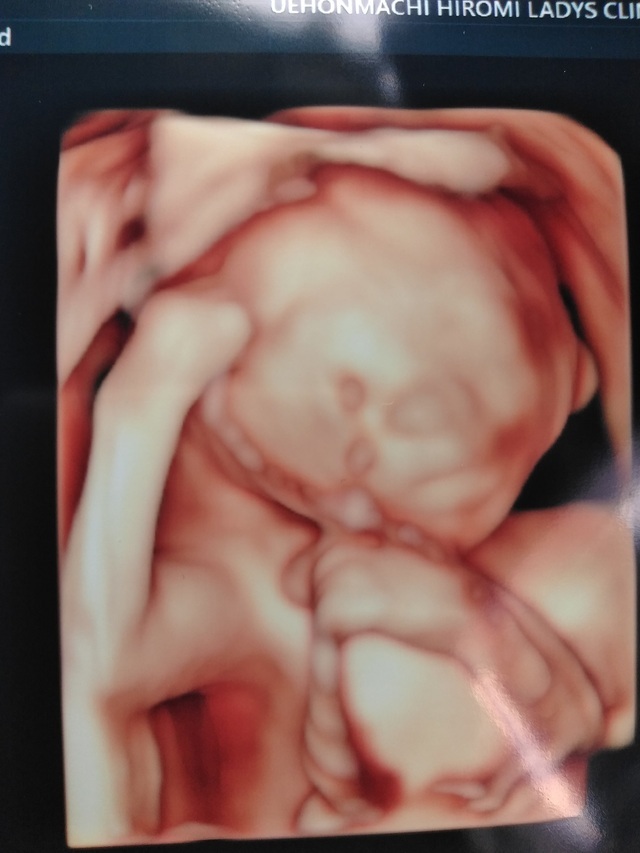

20週0日(20w0d・男の子)|saori 0104 さん

エコー写真撮影時のエピソード:

安定期に入った時に新居に引越しをし、病院を変えました。その時、初めての妊婦健診が胎児スクリーニングの時でした。胎児スクリーニングでは3Dエコーが見られるということで、初めての3Dエコーに私も主人も大興奮でした。助産師さんからは「この時期はみんな買おが一緒ですよ」と言われましたが、「このほっぺたが主人に似てる!」「鼻は私に似てるよね!」などと助産師さんお構いなしに盛り上がってしまったのはいい想い出です。

先程も記載した通り安定期に入った20週の頃にエコーを撮りましたが、私は妊娠悪阻で会社を1ヶ月半休職し、この頃は復帰して1ヶ月程たったときでした。今思うと1番体が動きやすく仕事もバリバリとやっていましたが、貧血が酷く電車の中で倒れることもしばしばありました。主人にはその度心配をかけさせてしまい、私の体調をすごく気にかけてくれました。健診には毎回ついてきてくれるので、一緒に赤ちゃんが産まれてきてくれることを楽しみにしてくれているんだなと感じます。